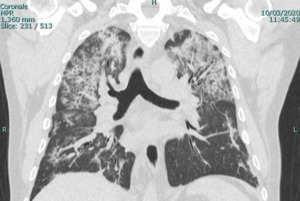

During this study, the three main types of imaging abnormalities include: a) ground glass opacities (i.e., hazy opacities that don’t obscure the underlying structures such as vessels), b) interlobular septa thickening (i.e., appearance of lines between lobes of the lung being more pronounced than usual),15 and c) crazy paving (i.e., finding of ground glass opacities with superimposed interlobular septa or intralobular septa thickening).16

Of the total 47 cases, there were 16 (34.0%) case reports with only a CT, two (4.2%) with only a chest radiograph, and 26 (55.3%) with both a CT and a chest x-ray. Ground glass opacities were noted for 33 (69.8%) of patients with a CT (Figure 1). Among case reports with a CT published, crazy paving was noted by the radiologist in 10 (20.9%) of the case reports (Figure 2) and thickening of the interlobular septa was noted by the radiologist in 14 (30.2%) of the case reports.

In the 33 (69.3%) of the cases with both a chest CT and a chest radiograph, the radiograph showed signs of COVID-19 (Figure 3). Most chest radiographs had non-specific findings, with the most common findings noted as hypotransparency (i.e., mild opacity in an area that should be transparent) or the radiologist documenting that the chest x-ray was consistent with COVID-19 without further detail. A total of 46 (97.8%) of the sample cases showed bilateral lung findings consistent with COVID-19 on CT. One (2.1%) patient x-ray showed only unilateral findings, with ground glass opacities being found in the left lung only. (Figure 4)

In our sample cases, ground glass opacities were found in 33 (69.8%) patients, crazy paving was found in 10 (20.9%) of cases and thickening of the interlobular septa was found in 14 (30.2%) of all cases. These proportions are each consistent with a 2020 radiological study focusing on CT with 81 patients in China.18 Although our study findings aren’t specifically novel, they confirm that CT can be used to establish an initial COVID-19 diagnosis, especially when other diagnostic modalities have failed to confirm the condition and/or patients’ clinical presentations may be ambiguous.